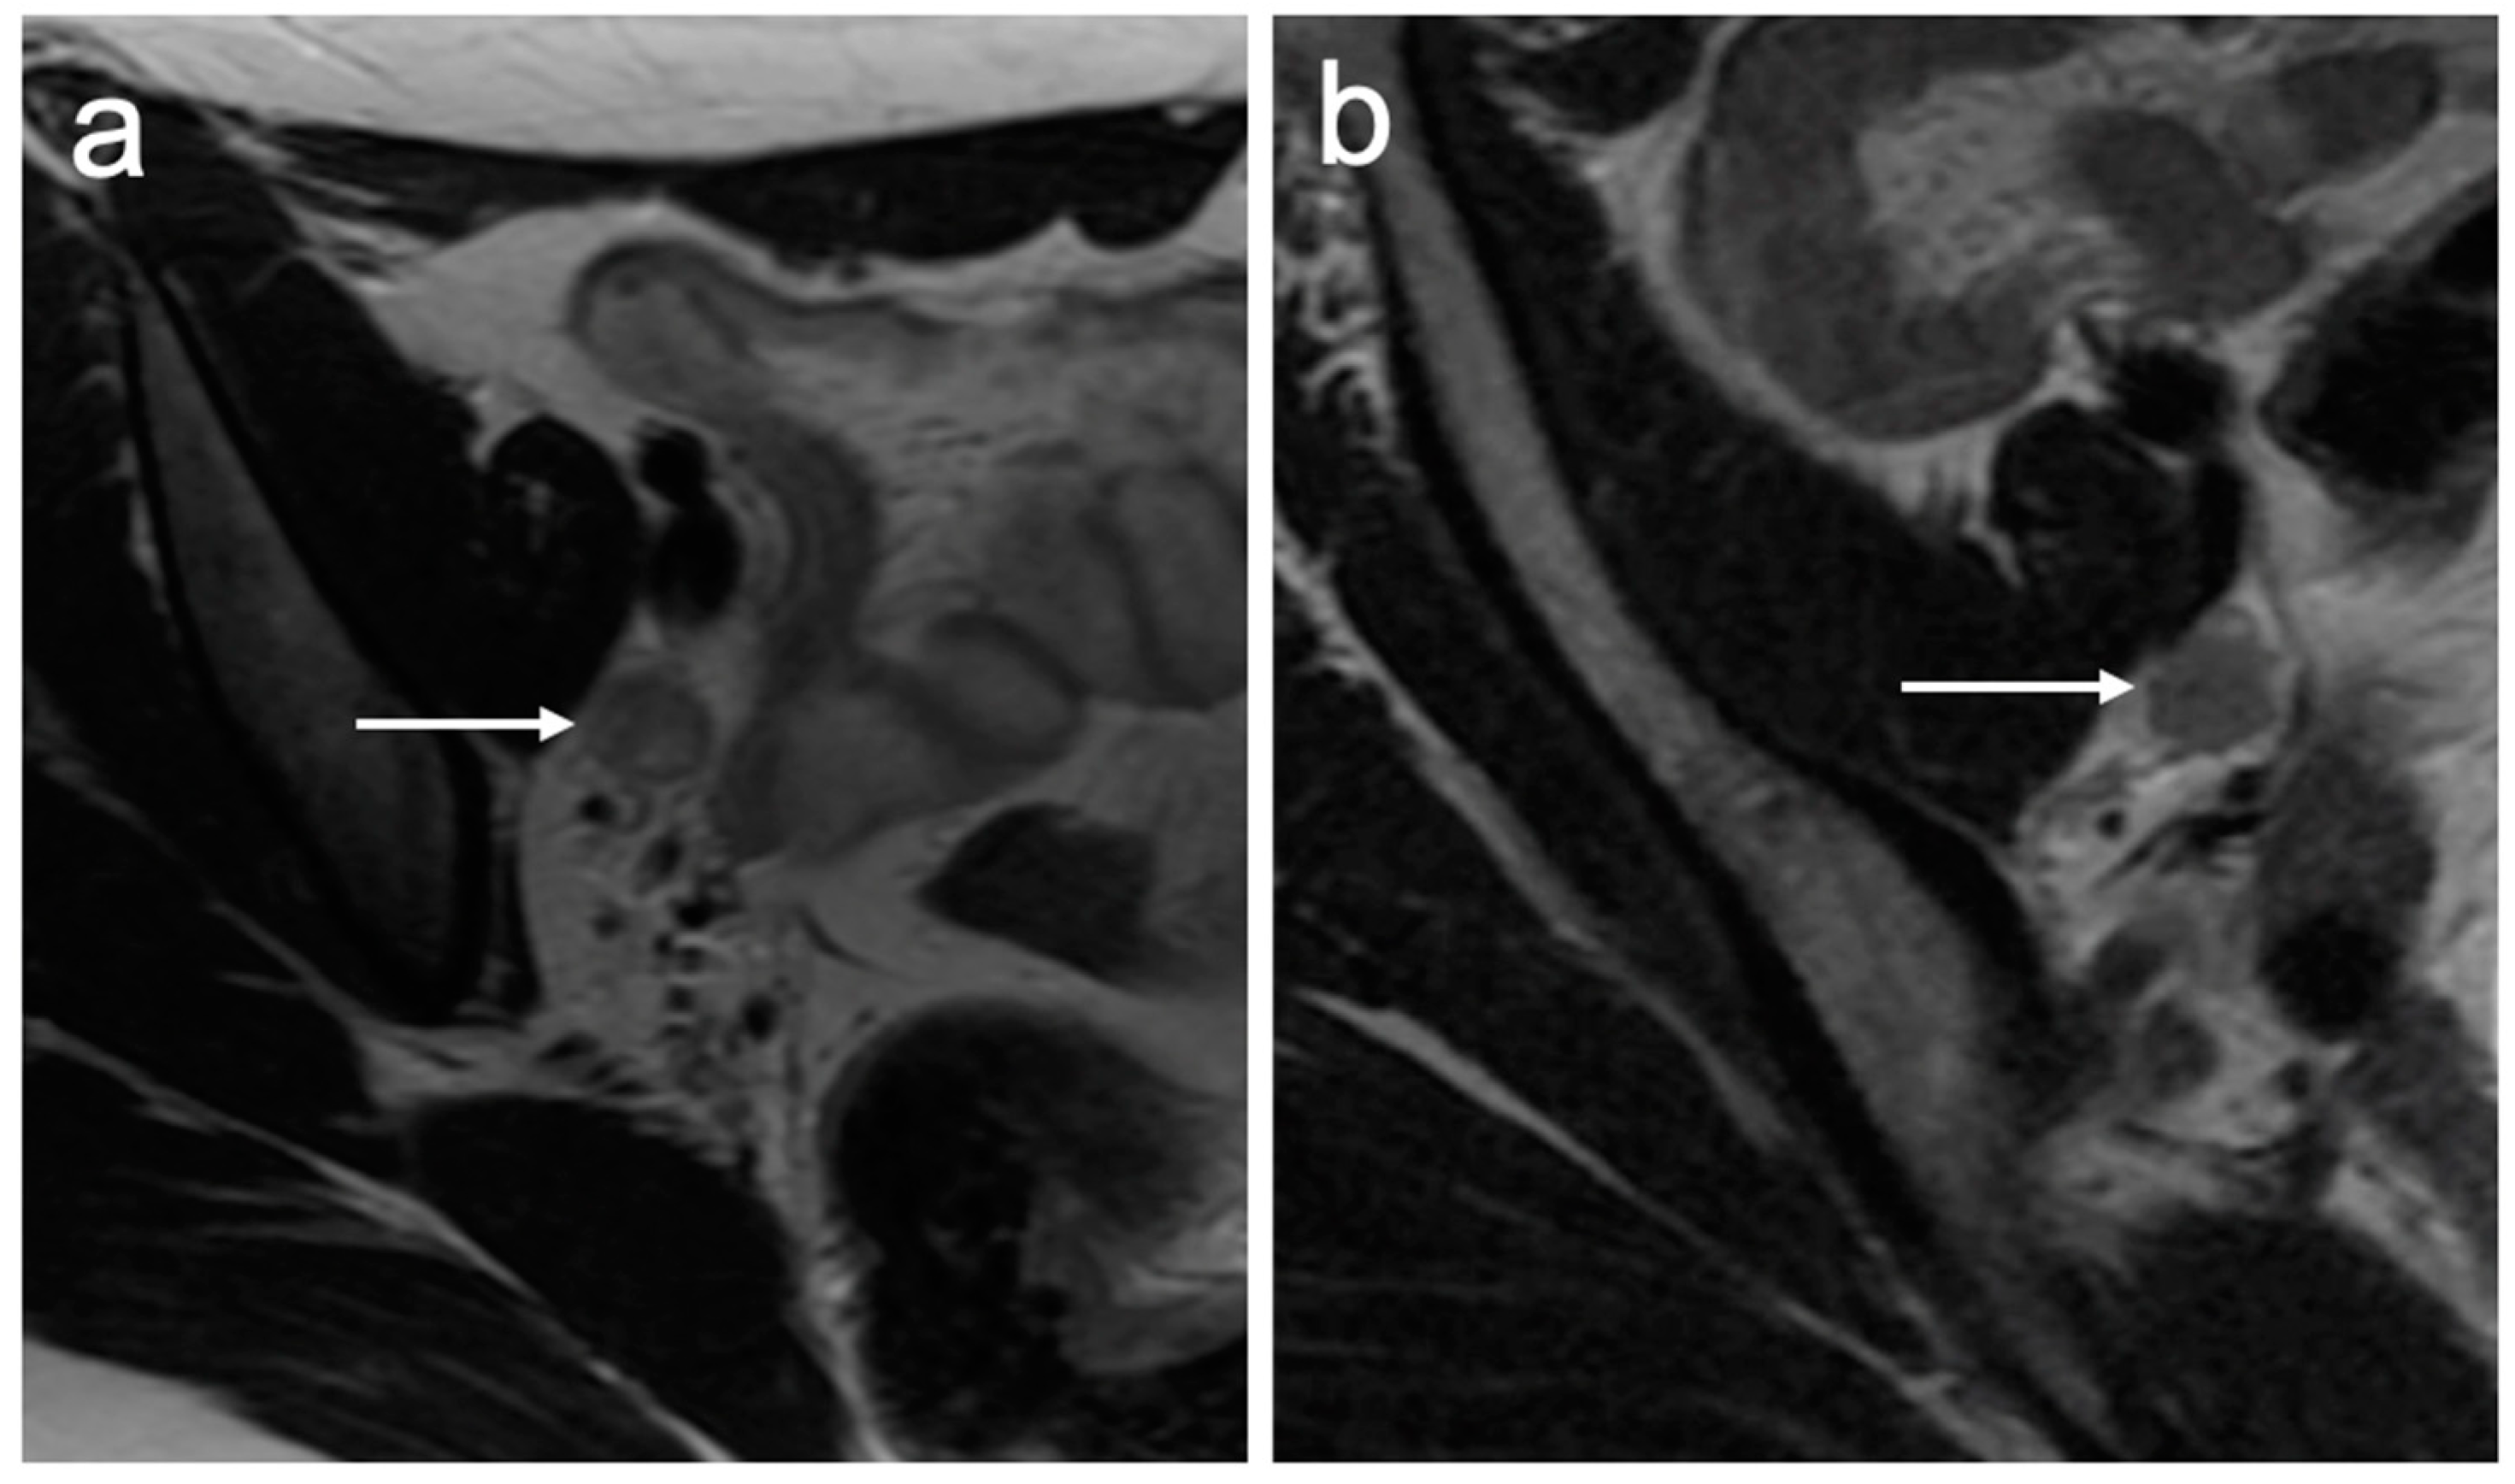

7. FIGO Stage IV

8. Impact of MRI Findings on Treatment Selection